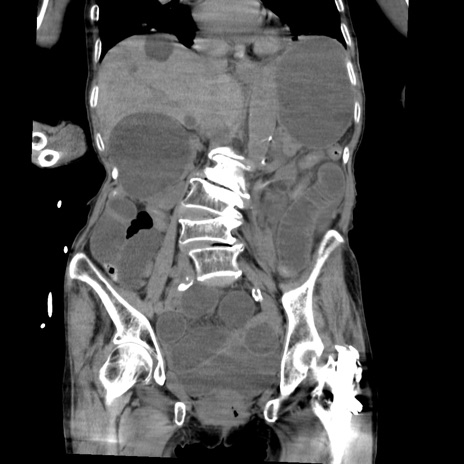

症例27(冠状断像)

【症例】80歳代女性

【主訴】嘔吐、腹痛

【現病歴】数時間前より嘔吐あり。心窩部痛出現し、徐々に右下腹痛あり。その後も数回嘔吐あり救急搬送となる。

【既往歴】左大腿骨頚部骨折手術

【身体所見】腹部は膨隆しているが軟らかく圧痛なし。腸雑音はやや亢進。

【データ】WBC 12000、CRP 19.05